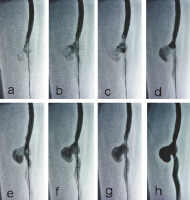

Pathologische Bypass-Hämodynamik

Abbildung 4a-h: Sequenzielle, angiographische Darstellung der pathologischen Bypass-Hämodynamik mit verzögerter Kontrastierung des postaneurysmatischen Bypass-Segmentes. Die Abbildungen a–h visualisieren einen Zeitabschnitt von 4 Sekunden. Darstellung der Kreiselströmung, des Milking-Phänomens und der Stase im Aneurysmasack.

Keywords: AngiographieBypass-Hämodynamik